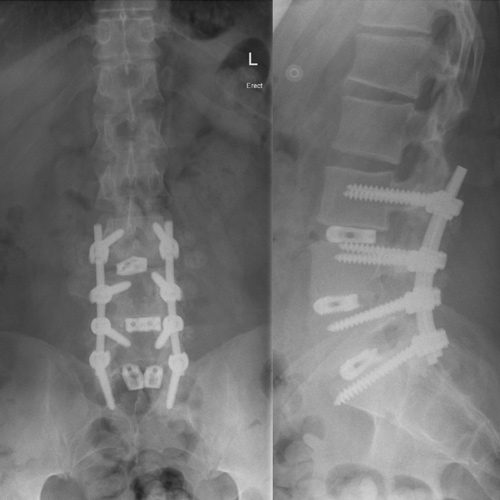

Spinal stenosis (Lumbar) Spinal stenosis (Cervical) Spinal stenosis (Thoracic) Lumbar Disc Herniation Spondylolisthesis Cervical Foraminal Stenosis Vertebroplasty Lumbar Fusion Anterior Cervical Fusion (ACDF) Posterior Cervical Fusion Thoracic Fusion Revision Lumbar Fusion Surgery Facet Joint Cyst Spinal Tumour Minimally Invasive Lumbar Fusion (XLIF) Minimally Invasive Lumbar Fusion (ALIF) Lumbar Fusion (TLIF) Thoraco-lumbar Fusion Lumbar Corpectomy Complex Lumbar Spine Surgery (Spino-pelvic fixation) Complex Cervical Spine Surgery Complex Thoracic Spine Surgery Occipito-cervical Fusion Minimally invasive surgery for thoracic disc herniation Other Related Topics